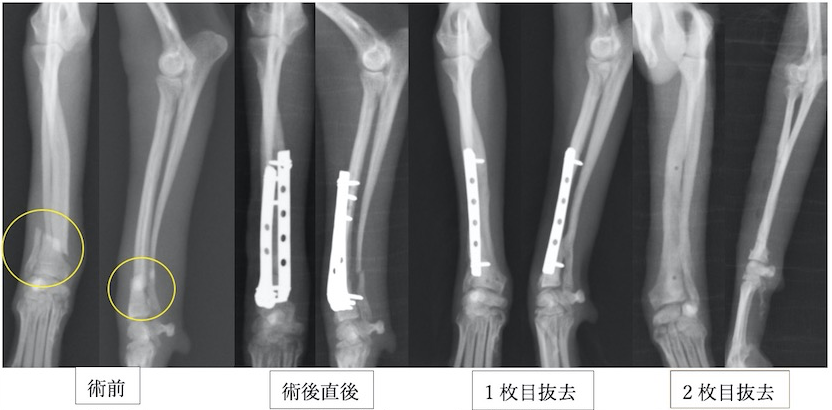

近年、小型犬が増加しているのに比例して橈尺骨骨折が増加しています。橈尺骨骨折にはプレートを2枚入れる方法を用います。2枚入れることで強度を増すことができプレートの破綻を防止できます。また、1枚ずつプレート抜去が可能であるため、ある程度骨が固まってきたら1枚抜去し、さらに骨化を促進し、もう一枚抜去するという方法が可能です。そうすることで癒合不全(骨化が遅れること)を防止し、プレート抜去後の再骨折のリスクを減らすことができます。

トイプードル9歳の橈尺骨骨折です。1.5mmスクリューを使用しています。

トイプードル2歳の橈尺骨骨折です。1.5mmスクリューを使用しています。 上の3症例ともにやや中央寄りの先端部の橈尺骨の横骨折(遠位骨幹部橈尺骨横骨折)です。直線のプレートを使用しています。